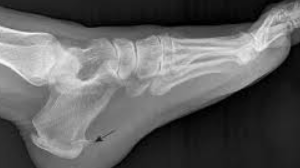

족저근막염은 발바닥에 있는 근막이라는 조직이 염증을 일으키는 질환입니다. 이 근막은 발뒤꿈치에서 시작하여 발가락까지 이어지는데, 주로 발의 아치를 지지하는 역할을 합니다. 족저근막염의 가장 흔한 증상은 발뒤꿈치의 통증이며, 특히 아침에 첫 발을 디딜 때 또는 오랜 시간 서 있거나 걸은 후에 통증이 심해질 수 있습니다.